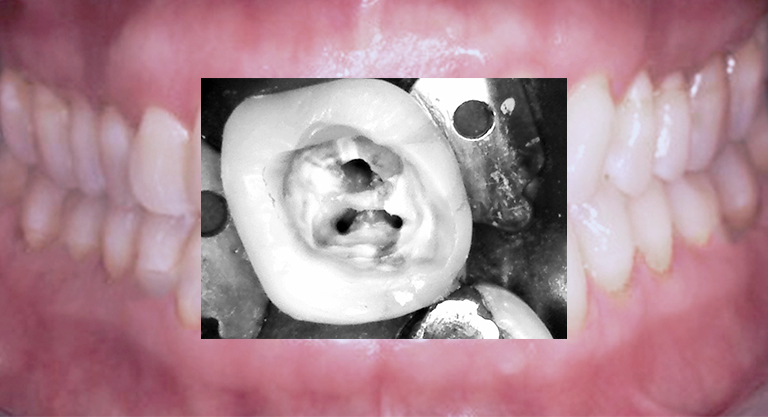

Restaurativ, konservierende Füllungstherapien

Endodontologische Therapie in Zusammenarbeit mit Fachspezialisten